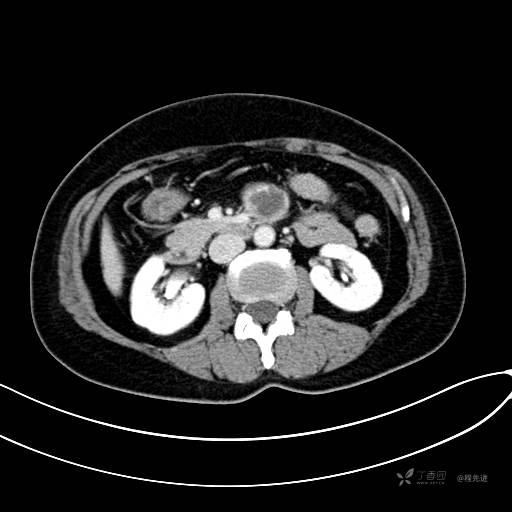

CT平扫